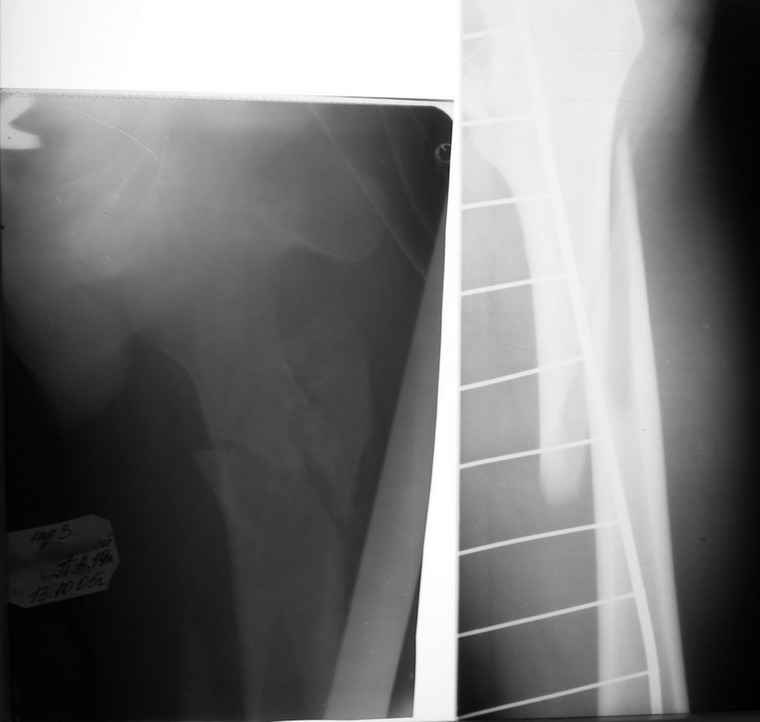

Если снимок справа по хронологии последний, то в тазобедренном сустава наступил анкилоз. Это хороший плюс костной ткани для постановки чашки эндопротеза, но отсутствие сохранения биомеханической оси бедренной кости ставит под вопрос благоприятный вариант усановки ножки эндопротеза.... Учитывая выполненную остеотомию, не считаю выполнение скелетного вытяжения лишенным смысла, для восстановления оси конечности с последующим, возможно, индивидуальным эндопротезированием.

Очень признателен Вам за ответ, но позвольте мне не согласиться с Вами. Я бы пока не делал вывод о анкилозировании тазобедренного сустава. На рентгеновских снимках, да и по данным компьютерной томографии (а этот метод один из самых современных и информативных), хорошо прослеживается постоянной ширины щель между головкой бедренной кости и вертлужной впадины. Кроме того, несложно увидеть разницу "шеечно-диафизарного угла" до и после выполнения тракции в аппарате. Хотя, Алексей, даже если я и прав, это не сильно облегчает нашу задачу.